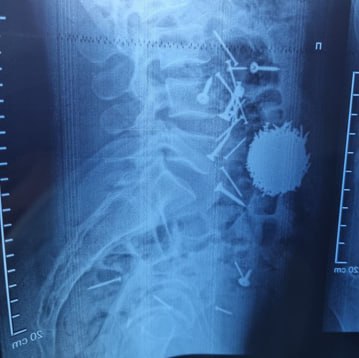

После проведённой диагностики и лабораторных анализов врачи обнаружили, что в желудочно-кишечном тракте пациента находится большое количество металлических предметов – гвоздей и саморезов. Ситуация требовала немедленного вмешательства.

«Мы определили, что пациенту необходимо экстренное хирургическое вмешательство. После всех подготовительных процедур была выполнена операция методом лапаротомии и гастростомии. Из брюшной полости удалось извлечь большое количество металлических предметов – около 200 граммов. Операция длилась примерно час. Сейчас состояние пациента хорошее, он свободно передвигается», – сказал он.